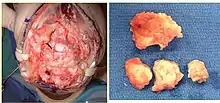

Surgery is generally indicated for displaced or unstable fractures.[18] The techniques of surgical management include open reduction internal fixation (ORIF), external fixation, percutaneous pinning, or some combination of the above. The choice of operative treatment is often determined by the type of fracture, which can be categorized broadly into three groups: partial articular fractures, displaced articular fractures, and metaphyseal unstable extra- or minimal articular fractures.[5]

Significant advances have been made in ORIF treatments. Two newer treatments are fragment-specific fixation and fixed-angle volar plating. These attempt fixation rigid enough to allow almost immediate mobility, in an effort to minimize stiffness and improve ultimate function; no improved final outcome from early mobilization (prior to 6 weeks after surgical fixation) has been shown. Although restoration of radiocarpal alignment is thought to be of obvious importance, the exact amount of angulation, shortening, intra-articular gap/step which impact final function are not exactly known. The alignment of the DRUJ is also important, as this can be a source of a pain and loss of rotation after final healing and maximum recovery.

If the fractures are unlikely to be reduced by closed means, open reduction with internal plate fixation is preferred.[5] Although major complications (i.e. tendon injury, fracture collapse, or malunion) result in higher reoperation rates (36.5%) compared to external fixation (6%), ORIF is preferred, as this provides better stability and restoration of the volar tilt.[5][23] Following the operation, a removable splint is placed for 2 weeks, during which time patients should mobilize the wrist as tolerated.[5]